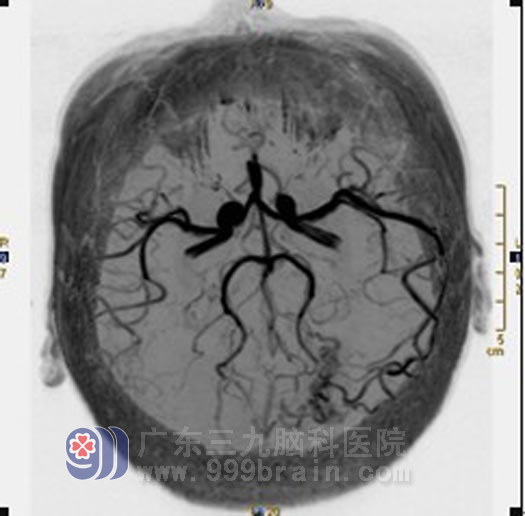

影像学(MRI+MRA)检查:

X-刀治疗前:左顶叶示片状异常信号影,T1WI呈低信号,T2WI以低信号为主,其内示小片状高信号影,FLAIR序列呈低信号,病变前上方示条状流空信号异常血管影。MRA显示左顶部可见畸形血管团影,左侧大脑中动脉远端增粗、延长并延伸至畸形血管团内。诊断:1.左顶叶动静脉畸形(左侧大脑中动脉参与供血);2.左顶叶脑出血后遗改变(软化灶形成、含铁血黄素沉着)。